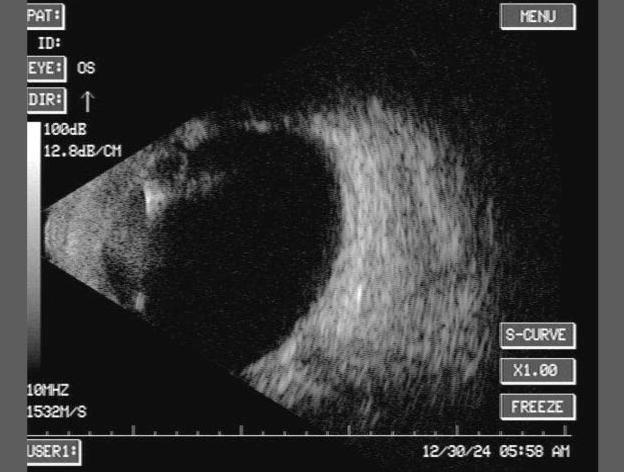

Impacto de los cambios refractivos en el cálculo del poder del lente intraocular en cirugía de cataratas

Autor: Dr. Pedro Luis Pichardo Longo1 Médico especialista en Oftalmología. Actualmente ejerce la práctica privada en el Centro de Tecnología Médica Avanzada (Cremedical) y en el Policlínico La Vega, República Dominicana.